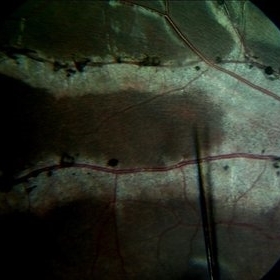

Choroidal Osteoma With CNV

Feb 28 2024 by stephen oconnell

23 year old male with 10 months of vision loss prior to presentation. Clarus 700 image of lesion with CNV and dependent subretinal fluid into inferior fundus.

Condition/keywords: macular choroidal osteoma